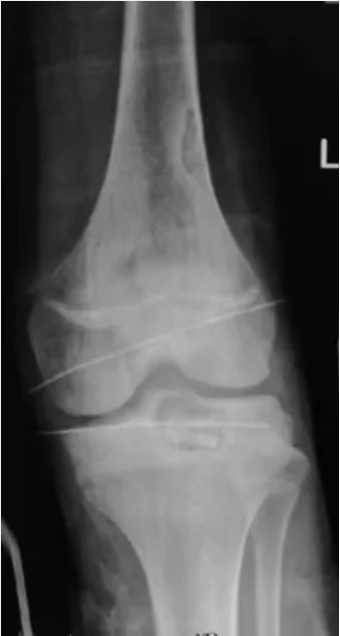

影像检查:

膝关节X线:左胫骨近端骨质密度不均影,可见溶骨性病灶改变,符合植骨后病灶复发。

CTA: 左侧胫骨平台可见团片状稍低密度骨质破坏影,直径约3cm,累及关节面,其内可见相邻腘动脉分支参与供血。

MRI:左侧胫骨上端占位,范围约30*30*20mm,T1WI等低信号,T2WI等高信号,边界较清楚,增强后轻度不均匀强化,周围骨髓及软组织肿胀。内外半月板、前后交叉韧带及内外侧副韧带形态、信号均未见异常。